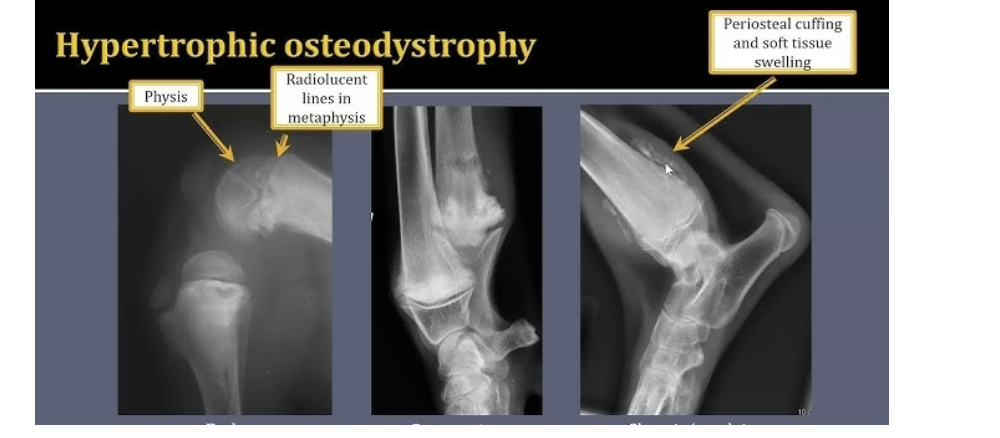

young musculoskeletal diseases: Hypertrophic osteodystrophy HOD

Developmental suto inflammatory disease

Unknown cause

Fast growing puppies of large giant breeds

Blood flow decreases to part of bone adjacent to joint

Interruption of bone formation

Bones dont harden correctly

Affects more than one leg at a time

Can permanently damage growth plates

Can be really painful

Self-limiting

How to diagnose HOD

PE and radiographs